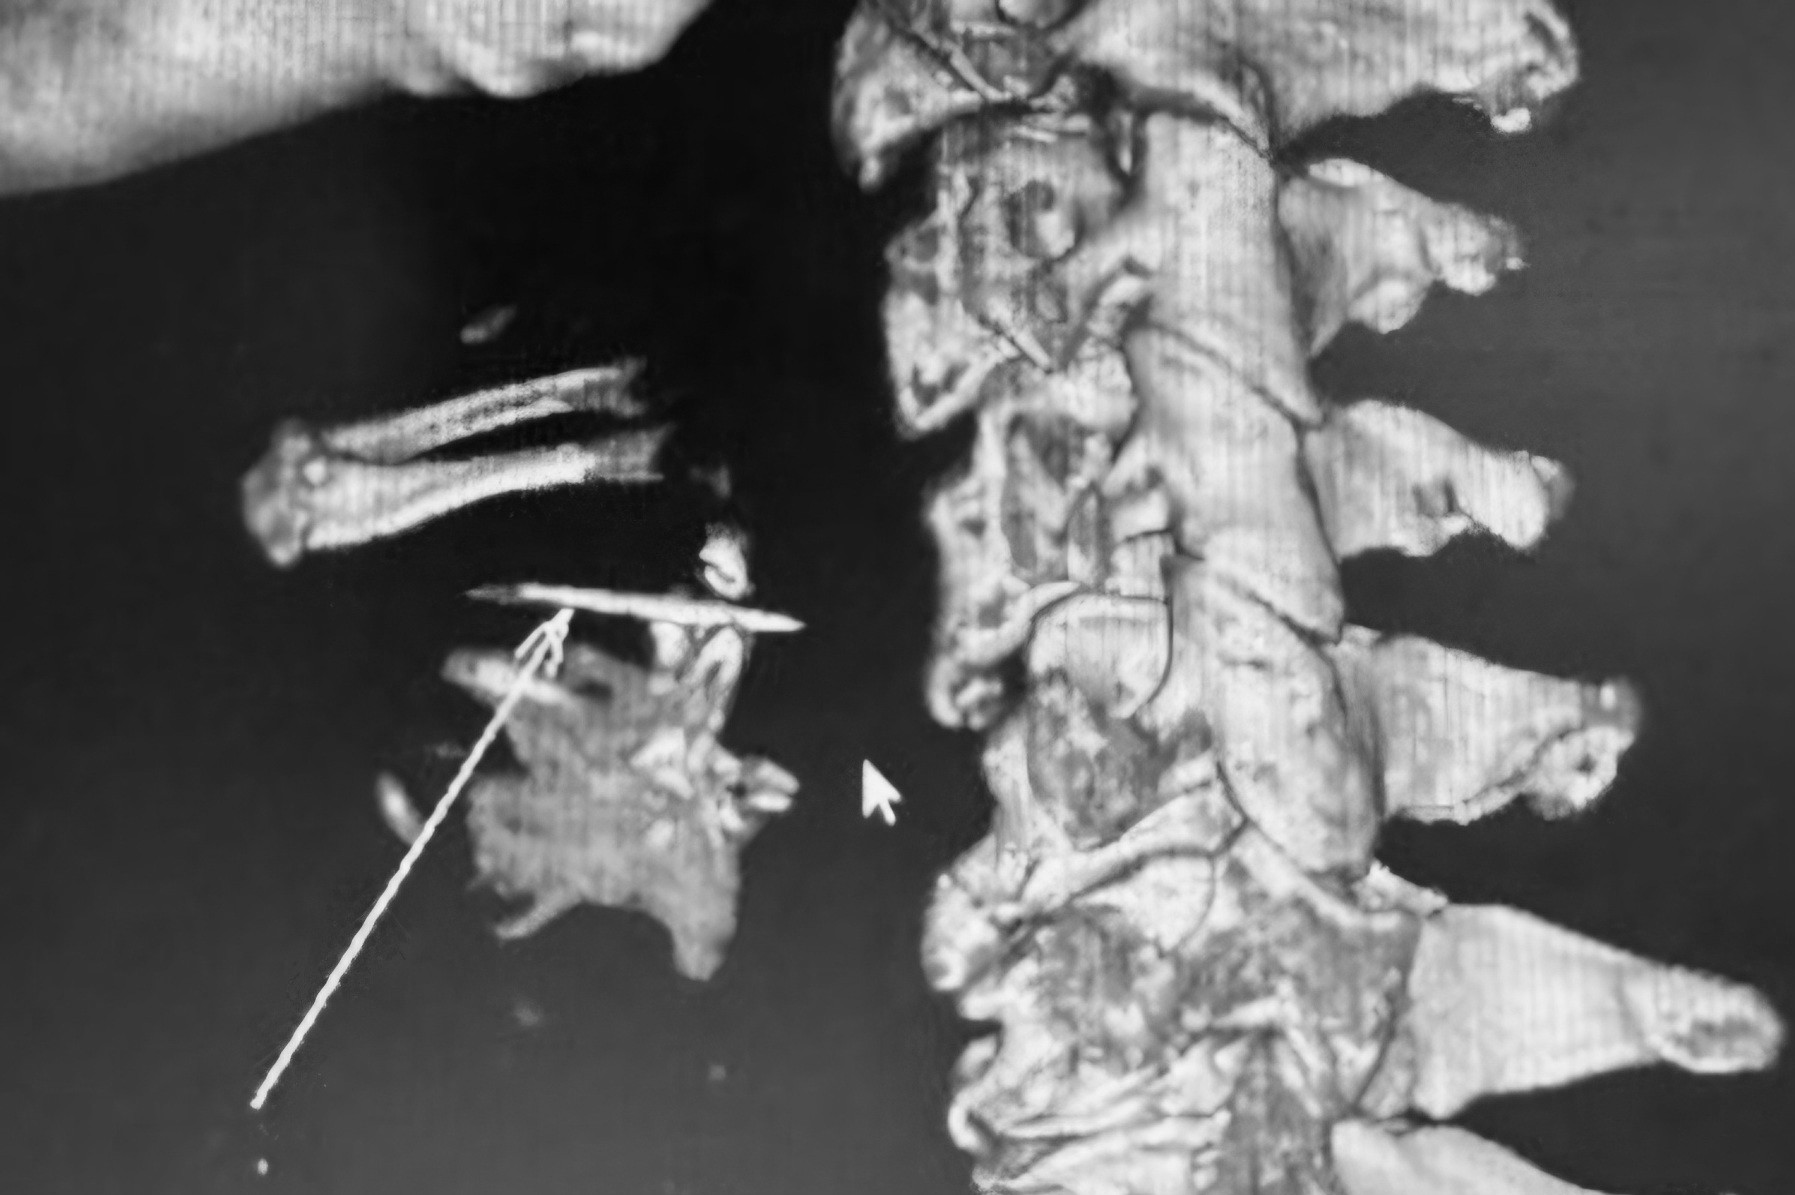

Nhận định đây là trường hợp hóc dị vật phức tạp, các bác sĩ chỉ định chụp cắt lớp vi tính 64 dãy có dựng hình 3D. Kết quả cho thấy xương cá nằm ở xoang lê bên phải, cạnh thành khí quản, ngang mức đốt sống C4. Đây là vị trí rất nguy hiểm vì dị vật có thể gây viêm nhiễm nặng tại chỗ và toàn thân; tổn thương thành họng, dẫn đến áp xe; tổn thương các mạch máu lớn; chèn ép đường thở, gây ngạt thở và tử vong.